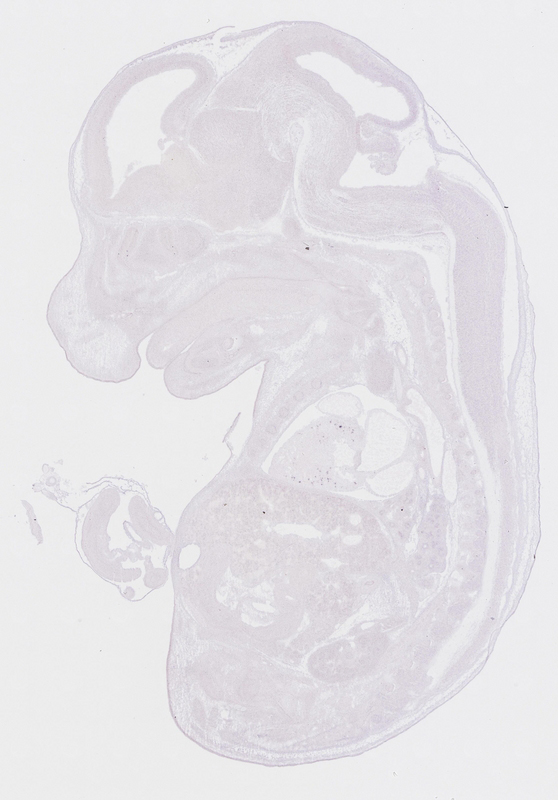

euxassay_002862_11:

embryonic day 14.5

euxassay_002862_12:

euxassay_002862_13:

euxassay_002862_14:

euxassay_002862_16:

euxassay_002862_17: